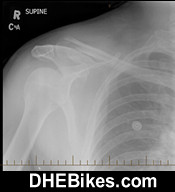

This is the pre-surgery x-ray of Downhill Dave's right shoulder. They should have operated at the hospital at the time of the accident but for some reason did not. 5 months after the accident the bones were still almost 2cm apart and would never fuse so surgery was required.

Shown above is Downhill Dave's badly broken left shoulder. Apparently the scapula was broken in 6 places and took a long time to heal. DH Dave also broke a few ribs at the same time and also shattered his downhill helmet in this crash...